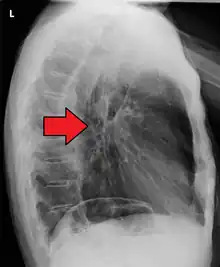

Esophageal cancer (lower part) as a result of Barrettʼs esophagus

Male predominance is particularly strong in this type of esophageal cancer, which occurs about 7 to 10 times more frequently in men.[25] This imbalance may be related to the characteristics and interactions of other known risk factors, including acid reflux and obesity.[25]

The long-term erosive effects of acid reflux (an extremely common condition, also known as gastroesophageal reflux disease or GERD) have been strongly linked to this type of cancer.[26] Longstanding GERD can induce a change of cell type in the lower portion of the esophagus in response to erosion of its squamous lining.[26] This phenomenon, known as Barrett's esophagus, seems to appear about 20 years later in women than in men, possibly due to hormonal factors.[26] Having symptomatic GERD or bile reflux makes Barrett's esophagus more likely, which in turn raises the risk of further changes that can ultimately lead to adenocarcinoma.[16] The risk of developing adenocarcinoma in the presence of Barrett's esophagus is unclear, and may in the past have been overestimated.[2]